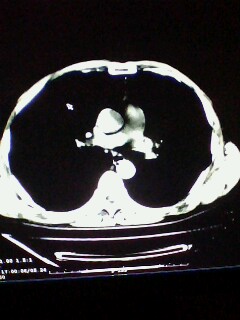

标题: CT28315:咳嗽咳痰咯血半月并胸痛 [打印本页]

标题: CT28315:咳嗽咳痰咯血半月并胸痛

左下肺肿块影,深分叶,考虑肺癌。

考虑左肺下叶周围型肺癌.

考虑左肺下叶周围型肺癌。

考虑左肺下叶周围型肺癌并阻塞性肺炎。